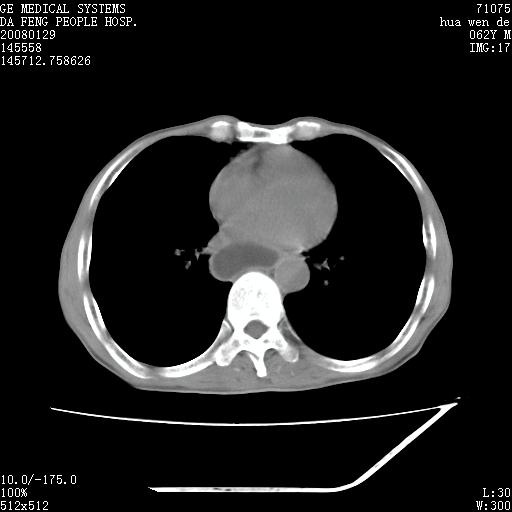

男性,67岁。作肺部检查时发现

理由:1、右上肺内病灶,空洞形成,有液平。

2、肺内多处炎症。

1.整个食管扩张,未见明显占位性病变,贲门区亦未见明显占位病变,考虑:贲门失驰缓症;

2.右上肺病变边缘可见毛刺,囊壁厚度不均匀,周围境界较清楚,未见炎性渗出性影,右上肺外带可见片状影,边缘不清,考虑:肺癌伴空洞形成、右上肺炎。

食管全程扩张,壁均匀不厚,喷门失弛缓症

右上肺空洞可见液平,临近肺野磨玻璃密度,考虑1.结核2.脓肿

贲门失驰缓症.肺部感染伴脓肿形成。支持!是否吸入性要结合临床诊断,我们影像是看不出来的。但胸腔胃能排除(1.没有手术史支持,2.双侧胸廓对称,胸壁、肋骨及胸膜规整,3,食管壁明显扩张内壁光滑,胸腔胃黏膜皱襞多较厚)。